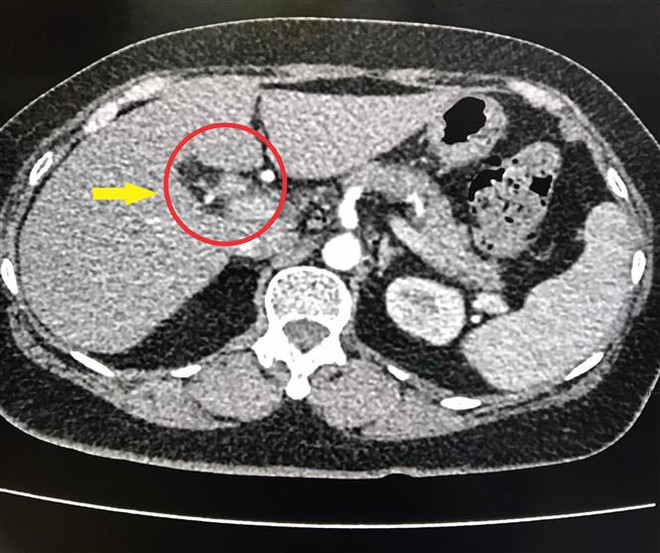

Bạc Liêu: Can thiệp thành công trường hợp tắc đường mật hiếm gặp ảnh 1Hình ảnh chụp CT về ca bệnh. (Ảnh: Chanh Đa/TTXVN)

Qua thăm khám sàng lọc kỹ lưỡng và thực hiện các cận lâm sàng cần thiết, các bác sỹ chuyên khoa chẩn đoán bệnh nhân bị tắc mật ngoài gan do khối u đường mật rốn gan (U Klaskin) ác tính - một loại ung thư đường mật vùng rốn gan hiếm gặp, không thể phẫu thuật triệt căn.